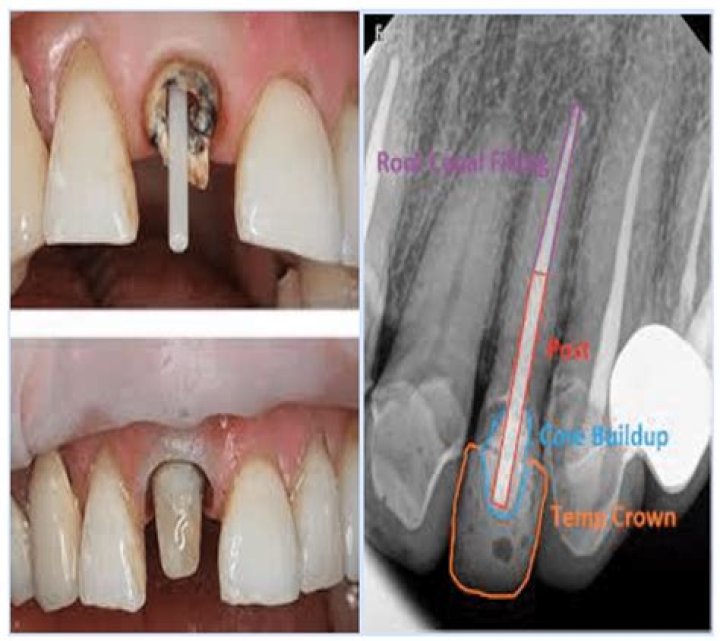

A core buildup is a restorative dental procedure that involves replacing missing tooth structure with special filling material so that it can successfully support a dental crown. The filling is usually prepared in the mouth using tooth-colored composites.

When there is a large amount of missing tooth we usually rebuild it with a filling material which is called Core Buildup. The purpose of the core buildup is to replace missing tooth structure, create optimal geometry for the crown restoration and protect integrity of the tooth.

Is a post and core necessary?

The post and core are essential for reinforcing the tooth and creating a firm bond for a dental crown that lasts.

Core Buildup is indicated for teeth with significant loss of coronal tooth structure due to caries or trauma in which insufficient tooth structure remains to adequately retain an indirect restoration.